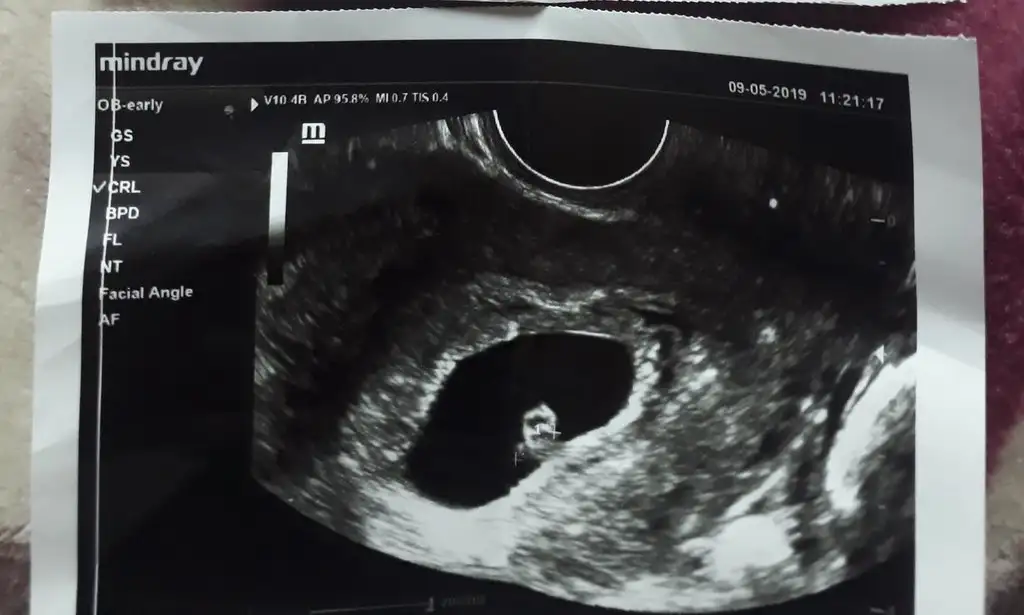

Benim vajinal usg görüntülerim 6+3 teyim. Yorumlar mısınız 😊😍

Kizlar banada yorum lutfen 1.resim 6 haftalik vajinal